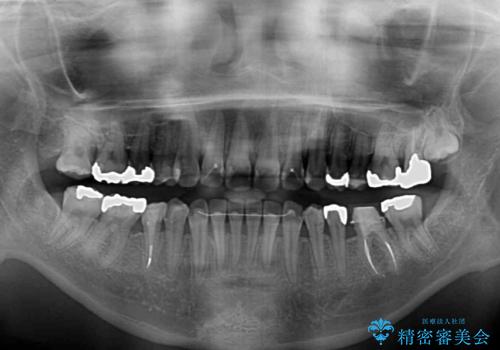

上顎骨拡大を併用したインビザライン矯正

- 上下のデコボコと奥歯の咬みにくさを気にして来院された患者様です。

上顎骨の幅が下顎骨よりも小さいので、拡大装置により骨幅を広げて上下関係を改善し、その後インビザラインにて歯並びを整えることとしました。

上下の骨幅を改善したことで、スムーズに歯列矯正を行うことができました。

矯正治療中に近医で銀歯を外す治療を開始したため、治療後に奥歯の咬み合わせが不十分ですが(こちらは近医での治療により改善するとのこと)、歯列と咬み合わせが改善され、患者様には大変満足していただきました。